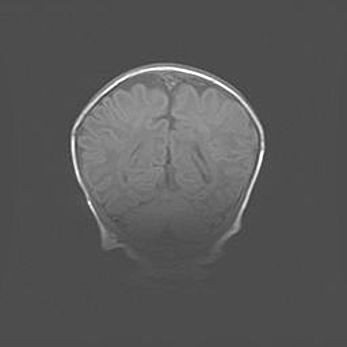

Множественные кисты обоих полушарий головного мозга, наибольшая из них в правой затылочной области. Ассиметричная атрофическая гидроцефалия.

Возраст: 7 месяцев

Вес: 5660 г

Пол: мужской

Окружность головы: 41,5 см

Срок гестации: 28-29 недель

Кисты головного мозга развиваются в результате многоочаговых некрозов вещества мозга и возникают вследствие перенесенной перинатальной инфекции, менингитов, энцефалитов, асфиксии, родовой травмы, расстройств мозгового кровообращения различного генеза. Образованию кист в веществе головного мозга плодов и новорожденных способствуют такие факторы, как высокое содержание в нем воды, недостаточная (или отсутствие) миелинизация и слабая астроглиальная реакция на повреждение.

Кисты могут сочетаться с гидроцефалией и другими поражениями головного мозга.